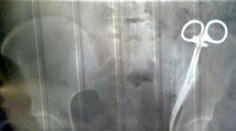

Chirurgia Viac ako 20 rokov má v tele chirurgické nožnice, zašili jej ich počas cisárskeho rezu Róbert Ďurkáč 19. 6. 2019

Lekári v tele ženy zabudli chirurgický nástroj veľkosti taniera. Prišlo sa na to po takmer dvoch rokoch TASR 5. 9. 2023